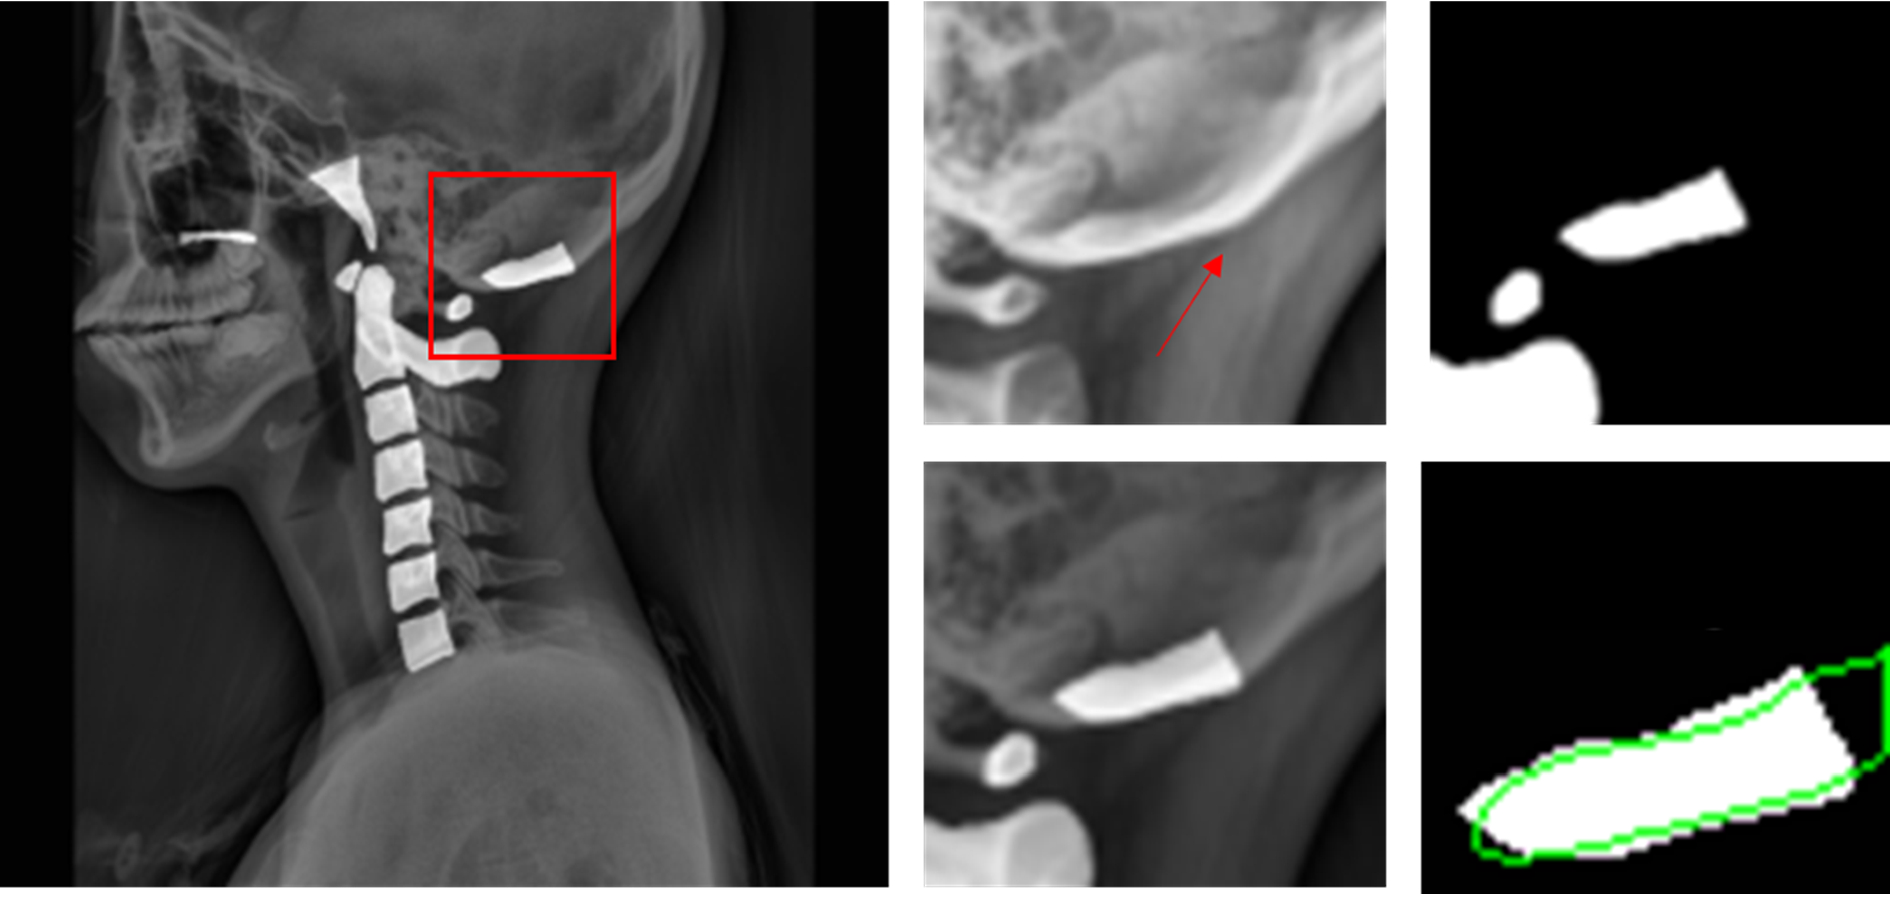

Figure 5

An example of obfuscated boundaries of an opisthion’s posterior end. Red arrow points to the ground truth boundary of the opisthion’s posterior end. The green outline shows an example of an AU-Net predicted opisthion mask, which extends further beyond the ground truth.